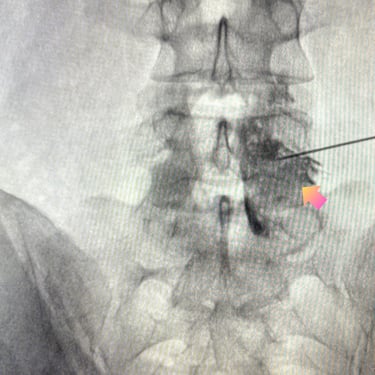

La discopatía lumbar y la espondiloartrosis forman parte del proceso degenerativo de la columna vertebral y pueden generar dolor lumbar persistente, irradiación hacia miembros inferiores y limitación funcional. Diversos estudios clínicos han demostrado que el bloqueo lumbar selectivo es una herramienta diagnóstica y terapéutica útil en estos pacientes. El procedimiento consiste en la infiltración guiada por fluoroscopía o ecografía de anestésicos locales y corticoides cerca de la raíz nerviosa o articulación facetaria comprometida. Esta técnica permite confirmar la fuente del dolor y disminuir la inflamación neural. En pacientes seleccionados, puede mejorar significativamente la calidad de vida y retrasar o evitar tratamientos quirúrgicos.